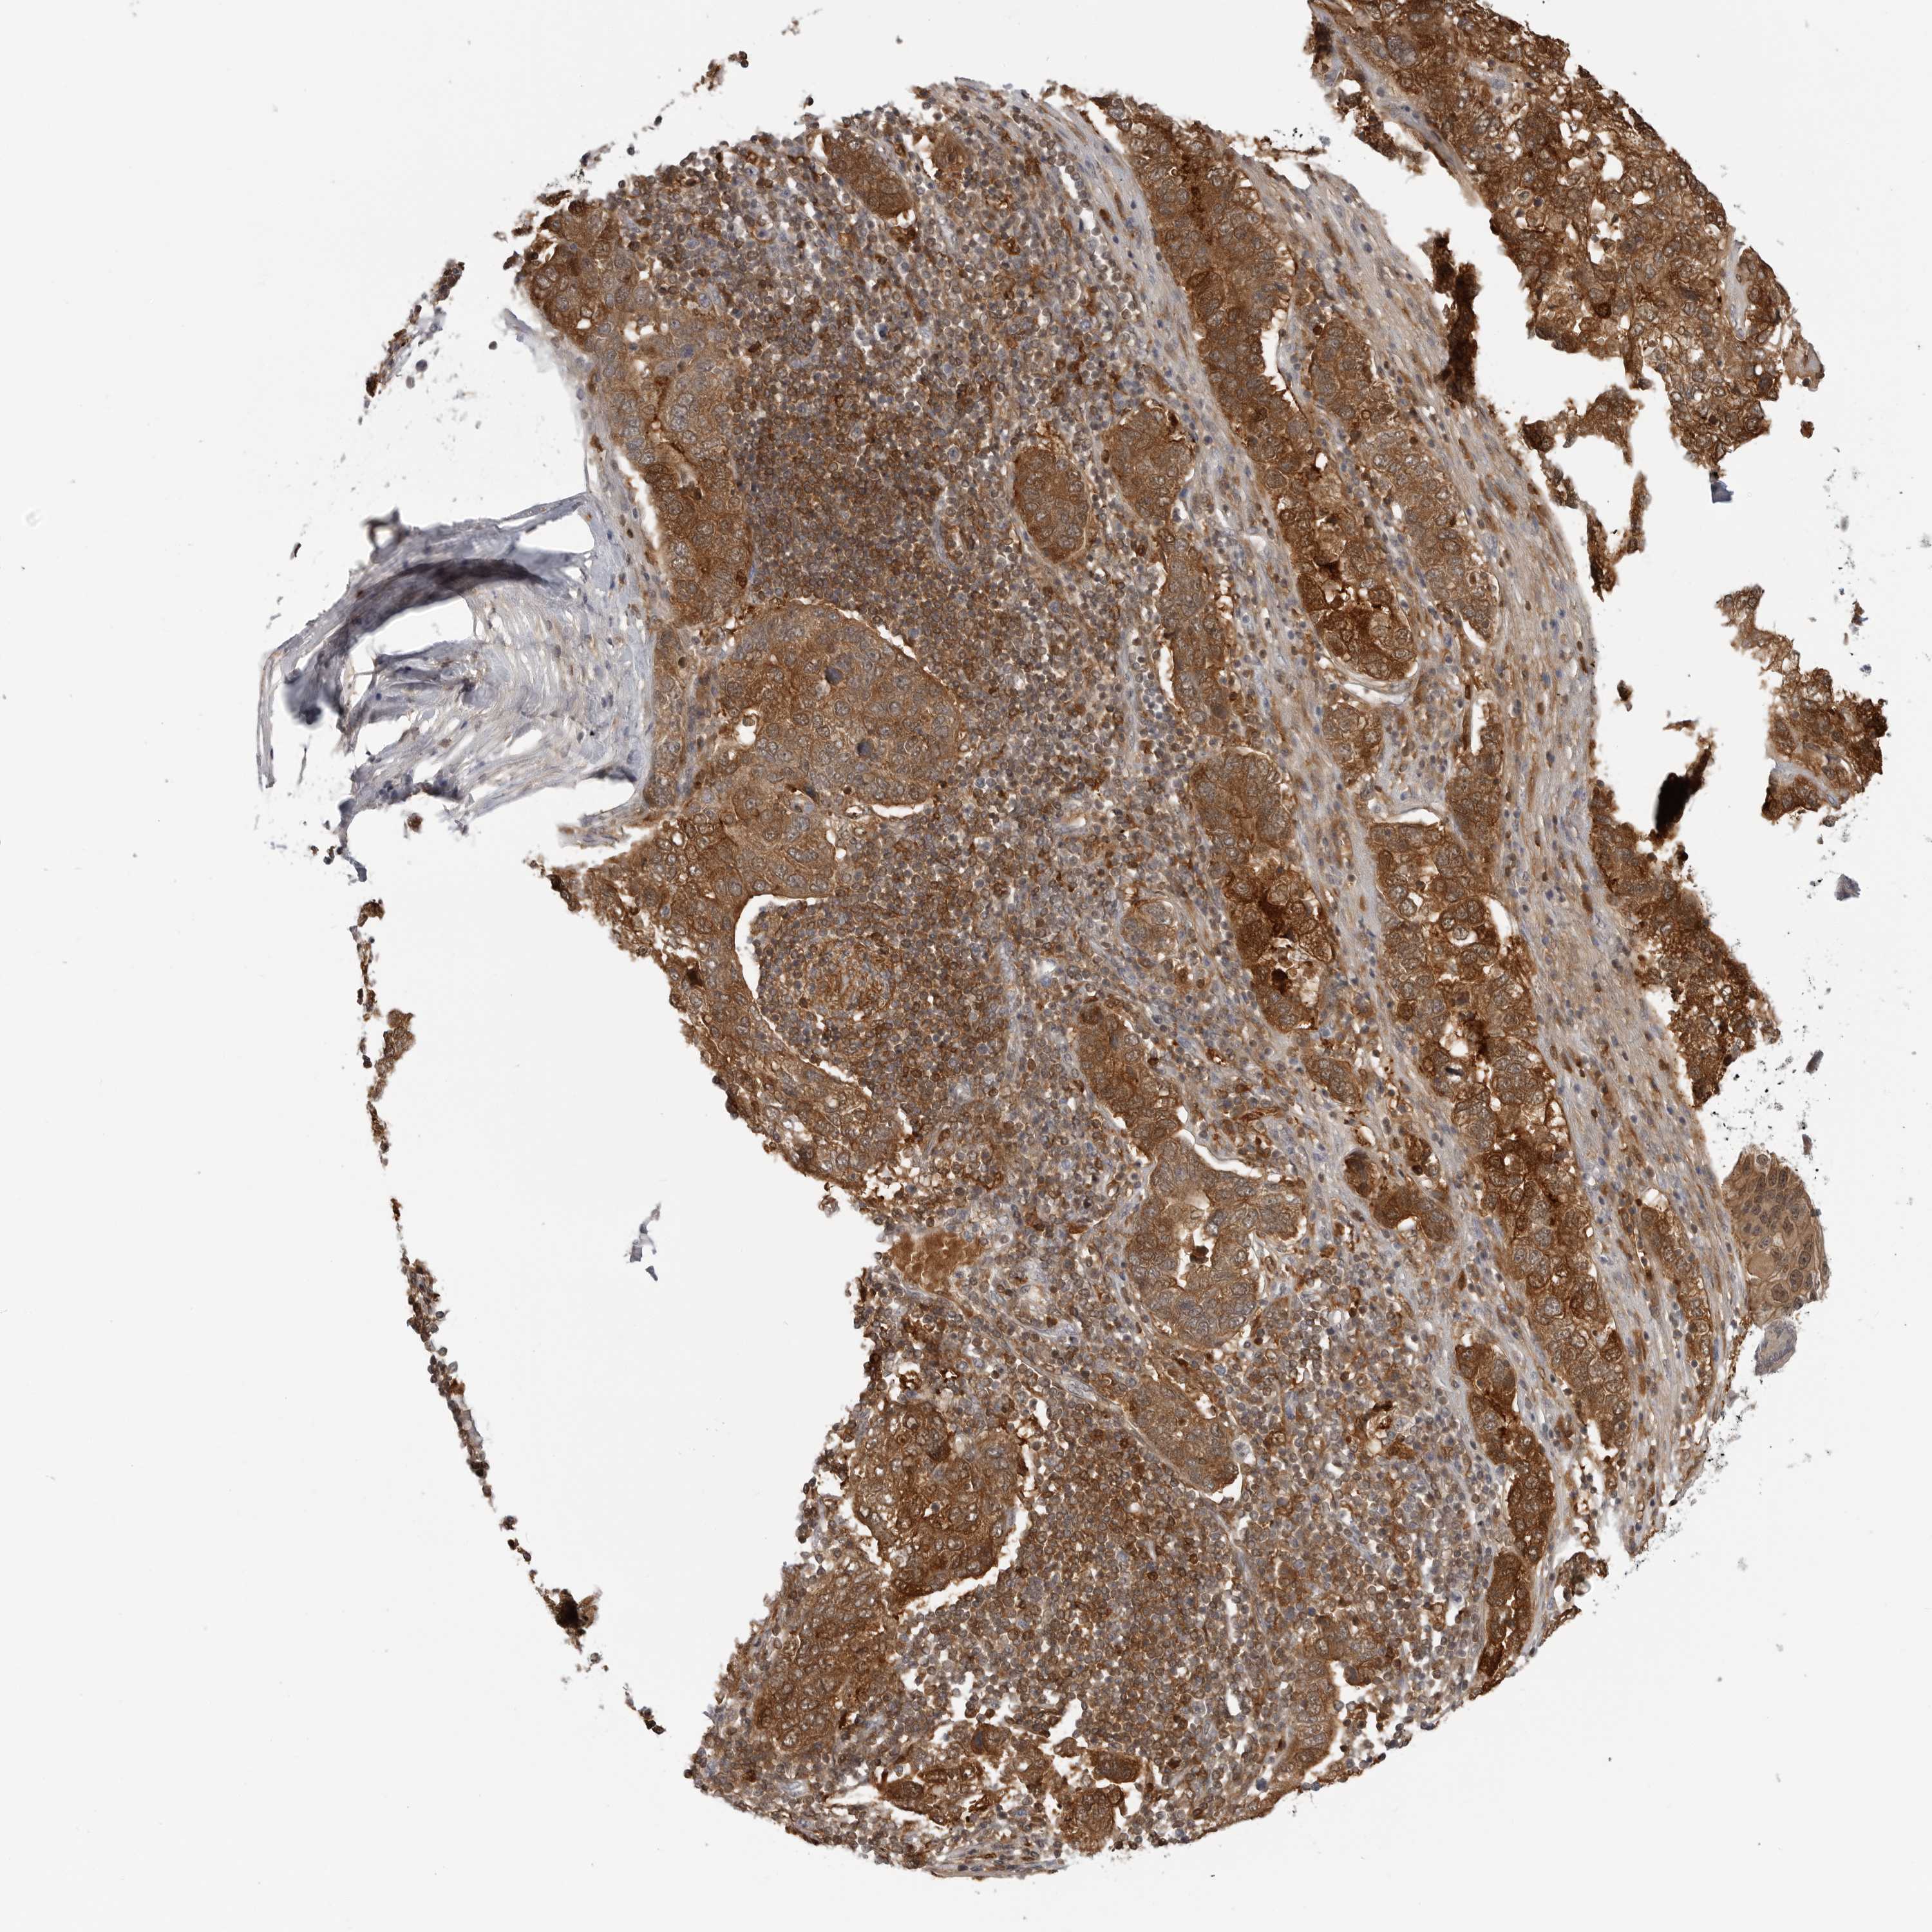

PANCREATIC CANCER - Protein expressioni

A mouse-over function shows sample information and annotation data. Click on an image to view it in a full screen mode. Samples can be filtered based on level of antibody staining by selecting one or several of the following categories: high, medium, low and not detected. The assay and annotation is described here.

Note that samples used for immunohistochemistry by the Human Protein Atlas do not correspond to samples in the TCGA dataset.

Antibody stainingi

Antibody staining in the annotated cell types in the current human tissue is reported as not detected, low, medium, or high, based on conventional immunohistochemistry profiling in selected tissues. This score is based on the combination of the staining intensity and fraction of stained cells.

Each image is clickable and will lead to virtual microscopy that enables deeper exploration of all samples and also displays staining intensity scores, fraction scores and subcellular localization as well as patient and tissue information for each sample.

Antibody HPA016865

Antibody HPA024801

Staining

High

Medium

Low

Not detected

Intensity

Strong

Moderate

Weak

Negative

Quantity

>75%

75%-25%

<25%

None

Location

Nuclear

Cytoplasmic/membranous

Cytoplasmic/membranous,nuclear

Adenocarcinoma, NOS